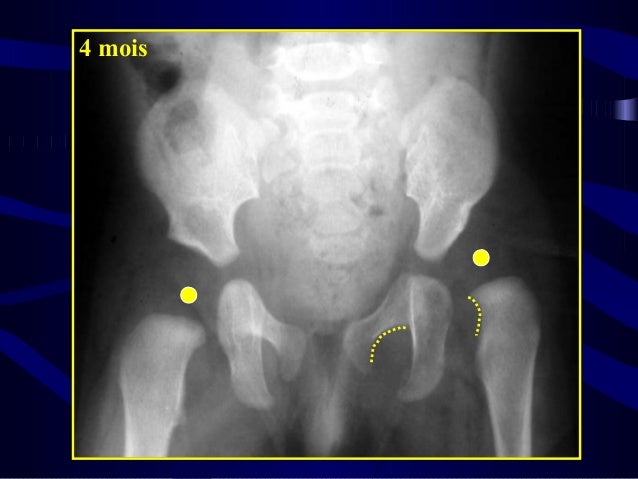

La radiographie est idéalement réalisée à l'âge de 4 mois, pour éviter les faux positifs dus à l'immaturité de la hanche Il s'agit d'une technique d'imagerie simple qui utilise des rayons X qui donne un accès rapide à l'analyse des parties osseuses du bassin et des hanches L'enfant est positionné fermement sur le dosEn cas de hanche douloureuse ou de boiterie, la radio n'est pas indiquée d'emblée si le diagnostic de synovite aiguë est retenu Elle ne devient nécessaire que si l'évolution n'est pas favorable en 48 heures au repos et sous antalgiques Des radios du basE16 –Les pathologies de la hanche de l'enfant I – La boiterie de l'enfant Les problèmes de hanche de l'enfant se manifestent essentiellement par une boiterie Le problème est l'analyse de cette boiterie et de connaître les causes de ces boiteries Elles sont un motif très fréquent de consultation en orthopédie pédiatrique

Rasta a grandit à l élevage , et rien pas une boiterie, visiblement pas de douleur, alors enfin arrivée à l'âge légal soit 12 mois , elle a passé une radio officielle des hanches, sous anesthésie c'est le protocole de dépistage de la dysplasie , chez un de mes vétérinaire comme tous mes chiensRéponse du Pédiatre Sur une radiographie, le noyau d'ossification de la tête fémorale peut s'apprécier à sept mois, avec des variations À l'âge de quatre mois, une radiographie permet de voir la structure du bassin et d'évaluer si la tête du fémur est bien positionnée dans l'acetabulum (cavité sphérique où elle vient seLa luxation congénitale de la hanche (LCH) est une anomalie du développement de la hanche qui se manifeste par une instabilité, c'estàdire une mobilité anormale entre le bassin et le fémur La tête fémorale sort, ou peut sortir, en partie ou en totalité, de la cavité articulaire du bassin